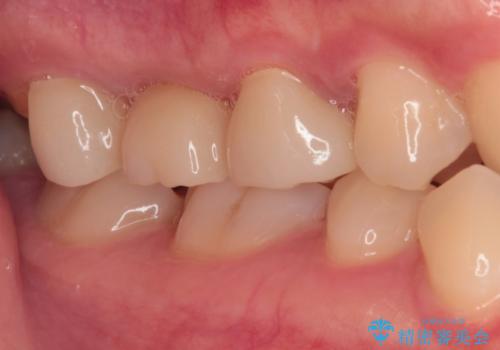

壊れやすいブリッジ インプラント治療で安定した咬み合わせに

- 頻繁に脱離を繰り返す奥歯のブリッジが欠けてしまったとのことで来院された患者様です。

外科処置を回避するためにブリッジ治療を選択されたそうですが、頻繁に脱離するので、欠けた部分のクラウンの作り替えと、欠損部のインプラント治療を行うこととしました。

最後方歯は、クラウンを維持するための高さが不足していたため、インプラント処置の際に歯冠長を延長する手術を併用し、維持力を増すこととしました。

上顎洞までの骨高さが低いケースでしたが、ショートインプラントと骨圧縮機能を持つドリルの使用により、上顎洞底挙上を行うことなく、インプラント治療を行うことができました。